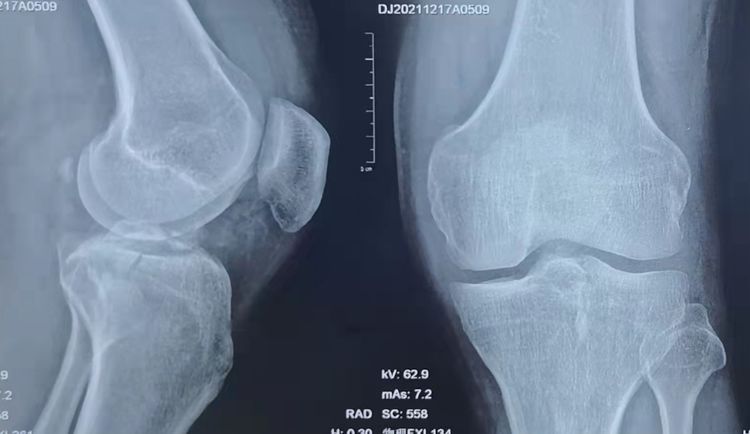

左膝正侧位DR:左膝前交叉韧带胫骨止点撕脱骨折,内侧胫骨平台骨折,均未见明显移位。

左膝CT

初步诊断:1、左膝ACL胫骨止点撕脱骨折 2、左膝胫骨平台骨折(Schatzker Ⅰ型) 3、左膝关节积液